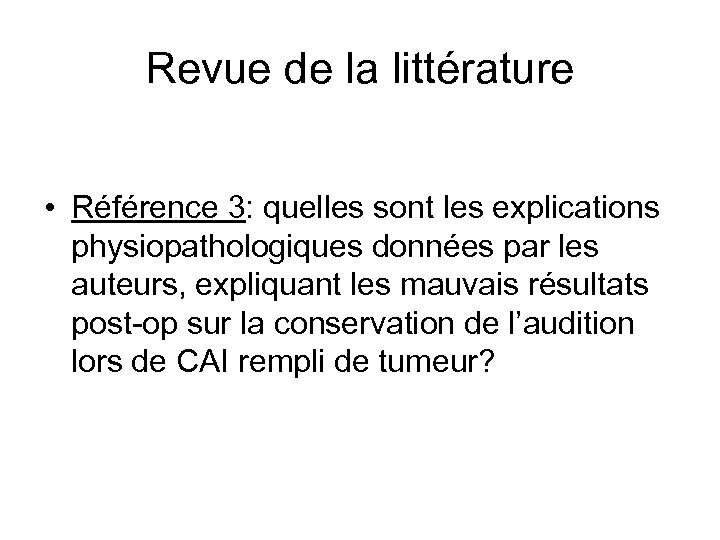

Revue de la littérature • Référence 3: quelles sont les explications physiopathologiques données par les auteurs, expliquant les mauvais résultats post-op sur la conservation de l’audition lors de CAI rempli de tumeur?

Revue de la littérature • Référence 3: quelles sont les explications physiopathologiques données par les auteurs, expliquant les mauvais résultats post-op sur la conservation de l’audition lors de CAI rempli de tumeur?